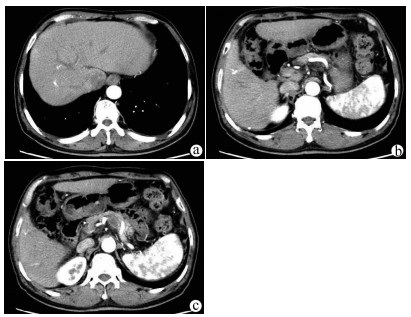

IgG4相关硬化性胆管炎临床特征及诊疗过程分析

李丽, 刘晖, 宋文艳

2021, 37(8): 1883-1887. DOI: 10.3969/j.issn.1001-5256.2021.08.026

摘要(1357) HTML (591) PDF (2114KB)(101)

摘要:

目的  观察IgG4相关硬化性胆管炎临床特点, 并对其诊疗过程进行分析。  方法  回顾性分析2014年1月—2020年9月在首都医科大学附属北京佑安医院诊断为IgG4-SC的25例患者的临床资料,通过电子病例系统采集患者基本信息、病史、诊疗经过、实验室检查、影像、病理资料。分析临床特征、确诊流程、误诊原因等。符合正态分布的计量资料用x ±s表示,非正态分布的计量资料用M(P最小值~P最大值)表示。  结果  25例IgG4-SC患者以男性为多见(21例,84%),平均年龄(57.61±9.73)岁,首发症状常见皮肤黄染和/或尿黄(18例,78.26%)、乏力(9例,39.13%)等。影像学分类:Ⅰ型16例(64%);Ⅱa型0例,Ⅱb型4例(16%);Ⅲ型1例(4%);Ⅳ型4例(16%),合并胰腺受累最多见(22例,88%)。治疗主要以糖皮质激素为主,2周内TBil平均下降67.48%。确诊的22例患者中,门诊拟诊“胆胰系统占位” 15例(68.18%),拟诊“梗阻性黄疸”5例(22.73%)。早期认识IgG4-SC疾病是通过术后病理,随后影像医师逐渐认识,最后通过多学科会诊方式使更多临床医生认识该病,患者得以更早确诊。  结论  对梗阻性黄疸的患者,临床医生需要结合临床表现尤其是影像学特点,对IgG4-SC进行鉴别。影像科、病理科、多学科会诊方式在帮助临床医师认识疾病、确定诊断方面发挥重要作用。